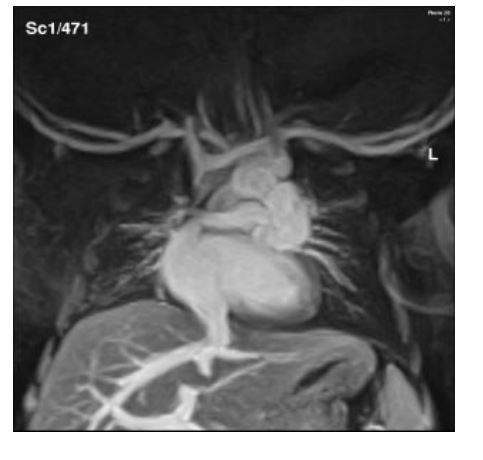

Anomalía parcial del retorno venoso sistémico Confirmación mediante resonancia magnética cardíaca

IMÁGENES EN CARDIOLOGÍA